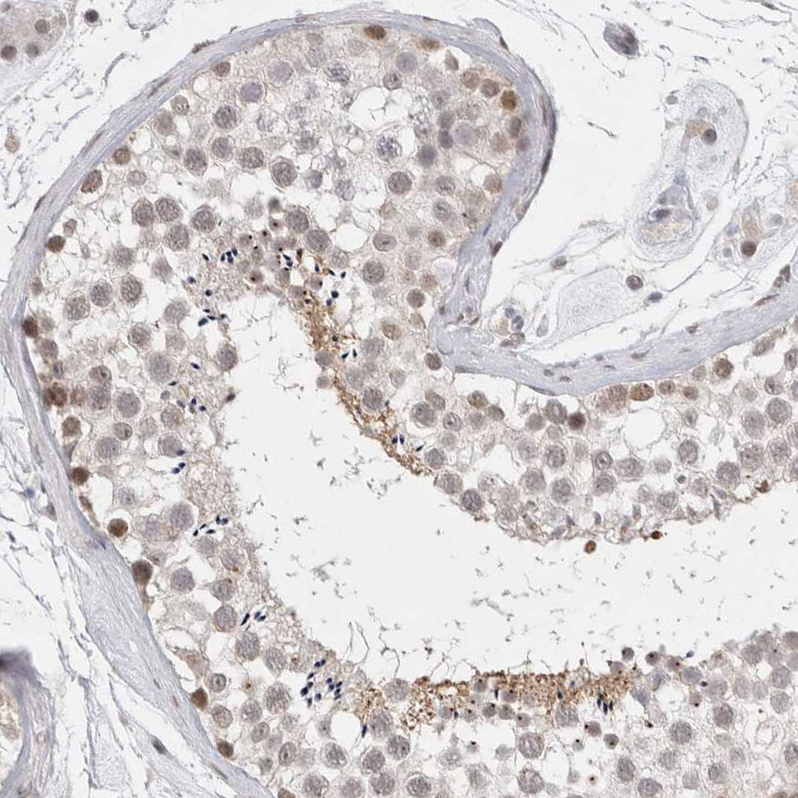

Immunohistochemical staining of human testis shows moderate nuclear and cytoplasmic positivity in cells in seminiferous ducts.